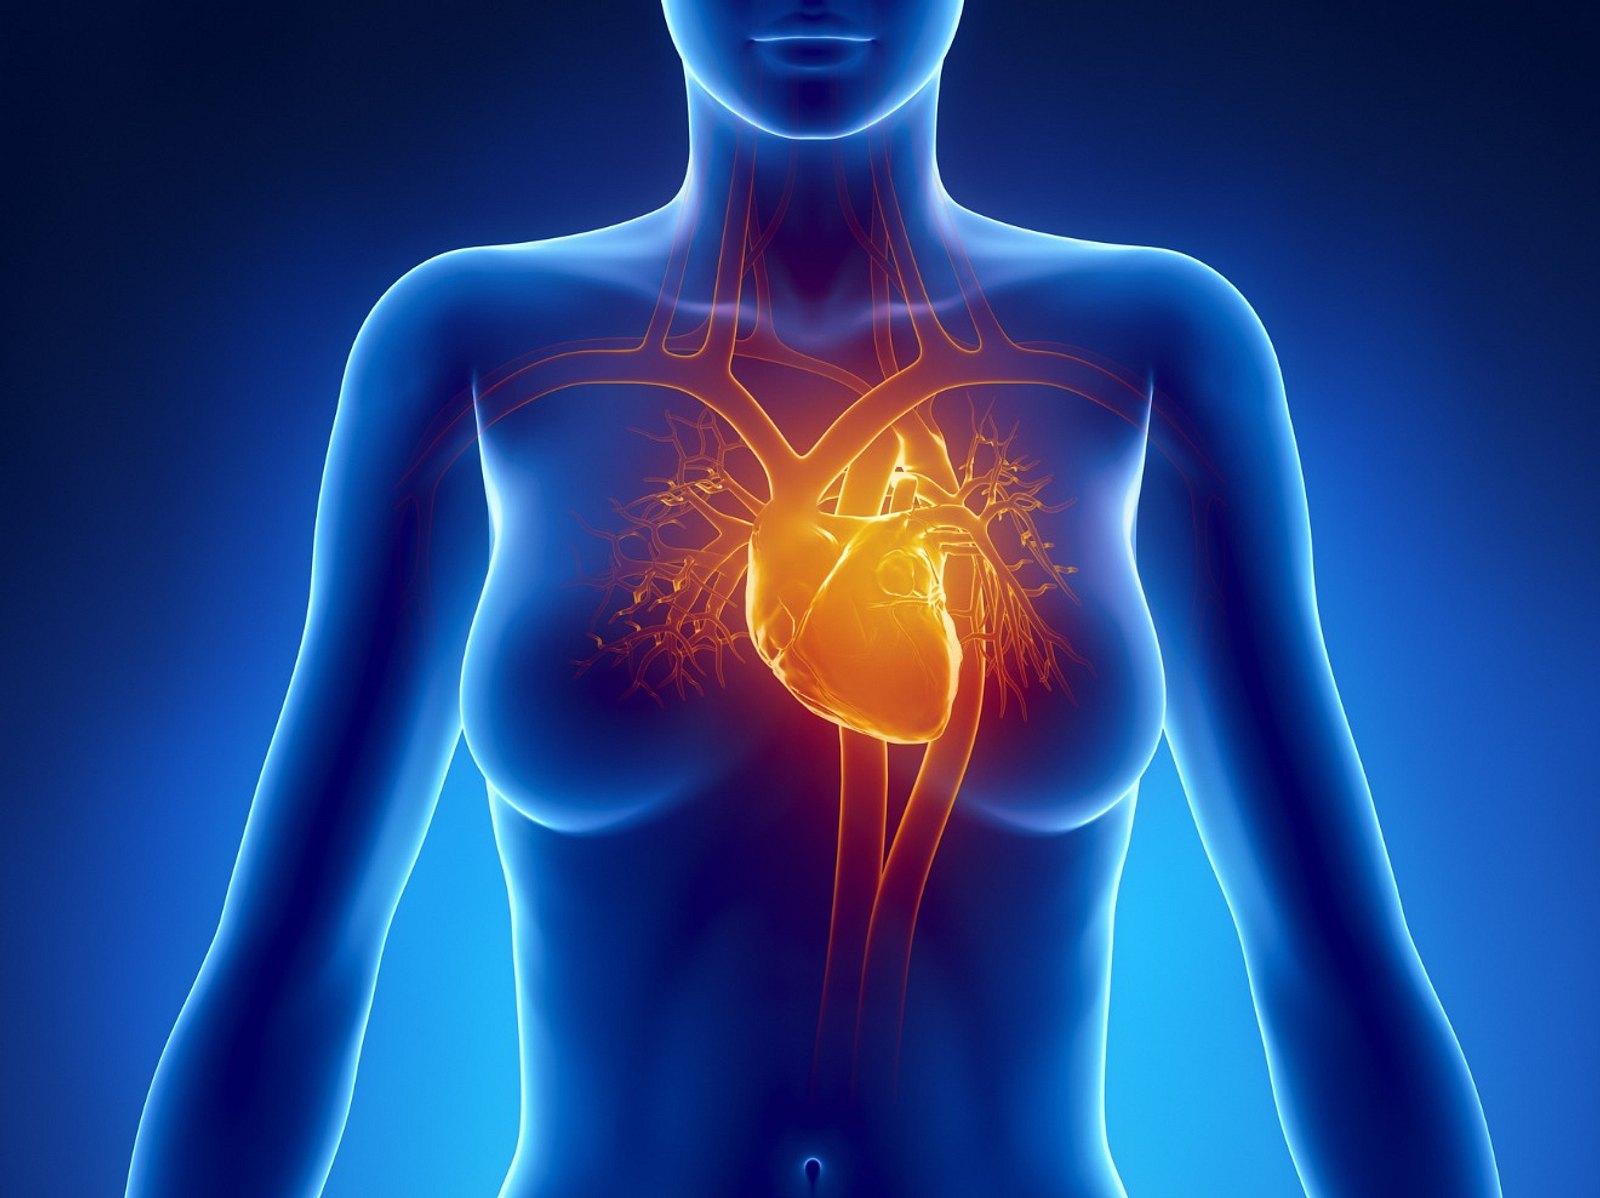

Где находится сердце у человека.

Сердце у человека располагается.

Сердце у человека располагается в грудной полости.

Расположение сердца у человека.

Анатомическое расположение сердца.

Сердце в грудной клетке расположено.

Где расположено сердце у человека анатомия.